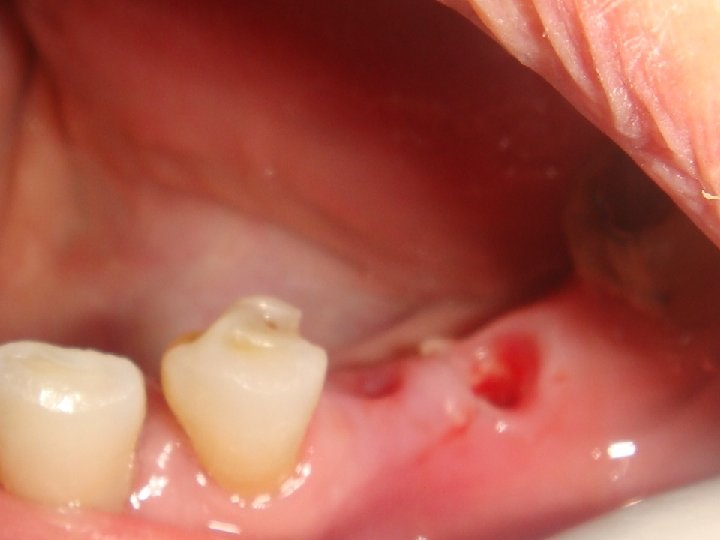

Abstract No. 1: A great challenge in implantology today is a predictable, long lasting red aesthetic result. An innovative treatment concept is based on a non-traumatic and effective shaping of the periimplant soft tissue – including an anatomical shaping from the first second. Especially, too many assembling and removing of abutments can contribute to aesthetic complications by vertical tissue loss. Therefore the “one abutment one time” and the “one crown one time” concepts are preferred. Additionally, platform switched and sealed implant-abutment connection prevent crestal bone loss and an apical shift of mid facial soft tissue.

Abstract No. 1: (cont. . ) In case of a fresh extraction socket the seal with the own tooth or a temporary crown can keep the complete soft tissue shape in a easy and predictable way. This "prosthetic" socket preservation simulates an intentional tooth reimplantation without the root. The same seal and therefore an optimal healing mode of the extraction socket is realized by an immediate implant insertion and restoration.